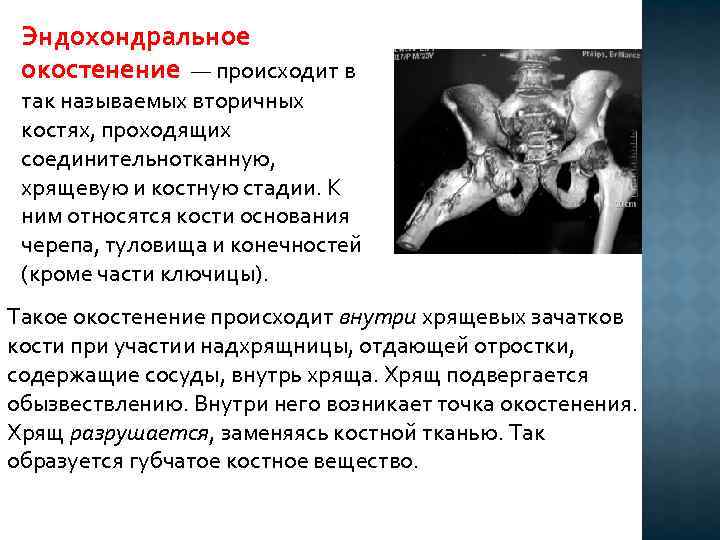

Эндохондральное окостенение — происходит в так называемых вторичных костях, проходящих соединительнотканную, хрящевую и костную стадии. К ним относятся кости основания черепа, туловища и конечностей (кроме части ключицы). Такое окостенение происходит внутри хрящевых зачатков кости при участии надхрящницы, отдающей отростки, содержащие сосуды, внутрь хряща. Хрящ подвергается обызвествлению. Внутри него возникает точка окостенения. Хрящ разрушается, заменяясь костной тканью. Так образуется губчатое костное вещество.